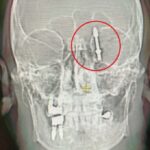

Nilüfer ilçesindeki özel bir diş kliniği, Yılmaz’a dişlerinin sallandığını söyleyerek implant önerdi. Doktor A.D.’nin uyguladığı işlem sırasında, implant vidası çene kemiğini delmek suretiyle kafatasına saplandı. Yılmaz, yaşadığı baygınlık sonrasında kliniğin aracıyla hastaneye kaldırılarak tomografi çektirildi. Çekim sonuçları, vidanın beynine kadar ilerlediğini gösterdi. Acilen ameliyata alınan Yılmaz, gerçekleştirilen zor bir operasyonla hayata döndürüldü.